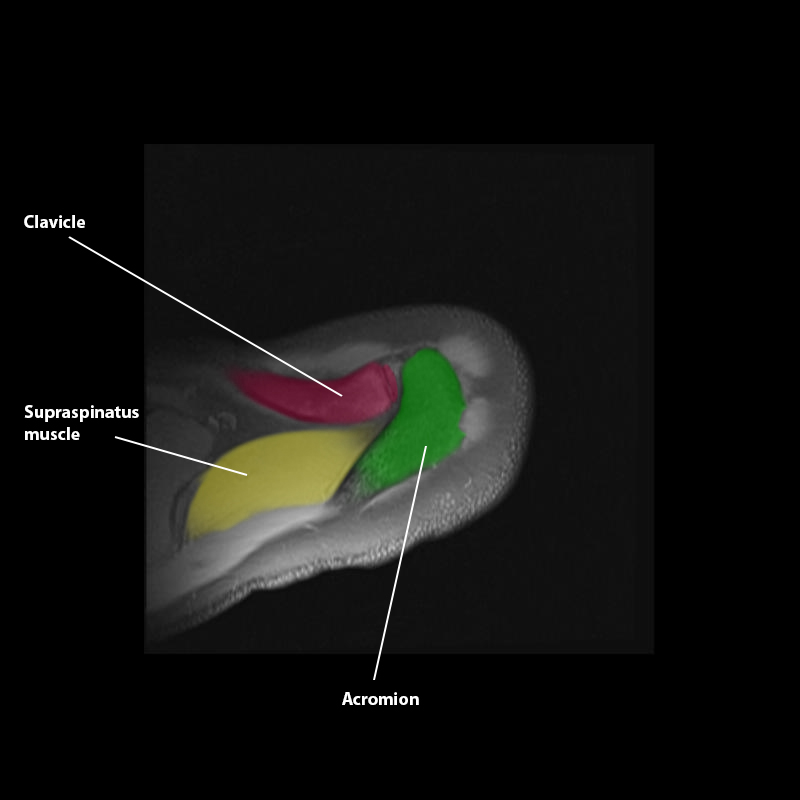

Shoulder MRI Anatomy